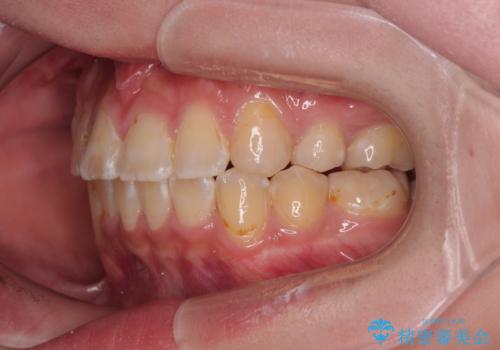

- 審美装置

- 八重歯や埋伏している奥歯など、多くの難しい問題を抱えている患者様です。

重度叢生のため、大臼歯をしっかりと咬合させるために、下顎は左右第二小臼歯を、上顎は前歯部の叢生を解消するために左右第一小臼歯を抜歯し、口元の突出感を改善するために、上顎大臼歯が前方に移動しないようにするために、補助装置による架強固定を行うこととしました。

叢生は思ったよりも早期に改善されましたが、舌の突出癖による上下前歯の非接触が全く改善されず、2年間ほど治療期間が延びる結果となってしまいました。